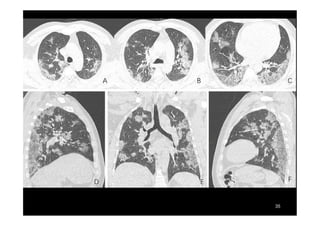

COVID-19 E O SISTEMA RESPIRATÓRIO

O vírus Sars-CoV-2 causa lesões extensas e severas em

múltiplas áreas dos pulmões, afetando principalmente os

alvéolos, as bolsas microscópicas nas quais ocorrem as trocas

de oxigênio e gás carbônico.

Tomografia mostra lesões nos dois pulmões, que aparecem como zonas esfumaçadas